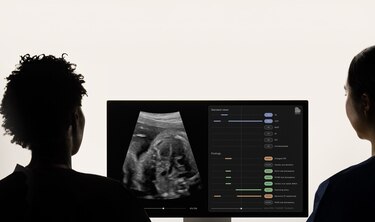

Así, al realizar un examen de ultrasonido antes del nacimiento, el ‘software’ analiza y procesa las transmisiones de vídeo mediante los algoritmos de IA entrenados. Es decir, evalúa en tiempo real la integridad del examen durante la captura de la ecografía y examina detalladamente la morfología del corazón fetal, realzando hallazgos sospechosos o confirmando su ausencia.

Con todo ello, con las capacidades de IA del nuevo ‘software’ de Brightheart, se espera que la tasa de diagnóstico prenatal de cardiopatías congénitas “aumente significativamente”, ayudando así a evitar posibles complicaciones después del nacimiento.